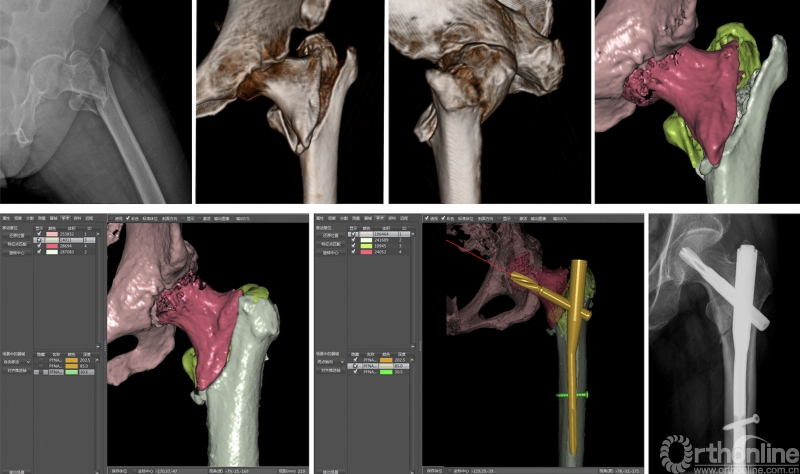

在髋部骨折的治疗中,股骨转子间骨折常用手术内固定方式包括股骨近端防旋髓内钉、股骨近端顺行联合拉力交锁髓内钉系统为代表的髓内固定系统,股骨近端解剖锁定钢板等髓外固定系统等。尽管上述内固定系统治疗转子间骨折取得了较理想的临床疗效,但术后并发症仍较常见,如股骨大转子外侧壁医源性损伤、髋内翻、螺钉切出、骨折移位及内固定失效等。上述困境使得骨科医生必须改善该损伤的当前治疗模式,而有效的术前计划可能会是解决这一临床难题的切入点。

陈雁西教授自2007年初开始,与计算机图像识别领域的专家经过2年努力,通过整合交叉学科前沿技术及大量的创新性工作,于2009年末共同创建出具有国际领先水平的“数字化骨科临床研究平台(SuperImage系统)”并成功实现产业化,相关成果发表在2009年11期《中华骨科杂志》上。作为国内骨科界权威杂志,特为本文新开一栏目“骨科前沿”,加长版面报道,引起骨科业内较大的反响。

SuperImage系统各个功能模块和相关技术指标迄今仍达到国际领先水平,该系统将医学影像科的定性诊断推向临床医生介入干预的精细、定量化诊断,辅助临床医生完成高仿真的术前设计,创建了全新的计算机辅助骨科(Computer-assisted Orthopaedic Surgery, CAOS)模式,明显提高了临床医生收集海量病例资料的工作效率。SuperImage系统为创建新型医疗模式、建立合理的临床路径及循证医学发展需求提供了必要的技术基础。

本研究中,陈雁西教授研究团队应用倾向性评分匹配法(Propensity-score Matching)有效控制混杂因素对观察结果的影响;对于缺失数据进行多重填补的同时,对研究结果进行相关敏感性分析,以确保因果推断结果的稳健性。通过与传统术前计划相比,发现基于计算机辅助虚拟手术技术的术前计划可降低老年股骨转子间骨折患者短期死亡率、术后并发症及再手术率;同时,可明显缩短年轻骨科医生对股骨转子间骨折诊治的学习曲线。

精准的术前计划可为医生提供全方位的骨折损伤细节观察、协助规划手术切口、选择适宜的内固定以减少术中透视的次数,从而缩短手术时间、提高手术精准度、减轻手术创伤,最终提高手术疗效。2018年,陈雁西教授团队在骨科领域TOP期刊《J Bone Joint Surg Am》以原创论著形式发表的研究就已论证了基于计算机辅助骨科技术的术前计划模式的便捷性和实效性,该文得到哈佛大学医学院教授在JBJS(am)同期撰文高度评价并提出该研究中的计算机辅助术前计划模式可改变国际骨科领域既往所有的术前计划方式。近日《JAMA Network Open》的发表再次论证了该类计算机辅助术前计划模式的临床应用价值。